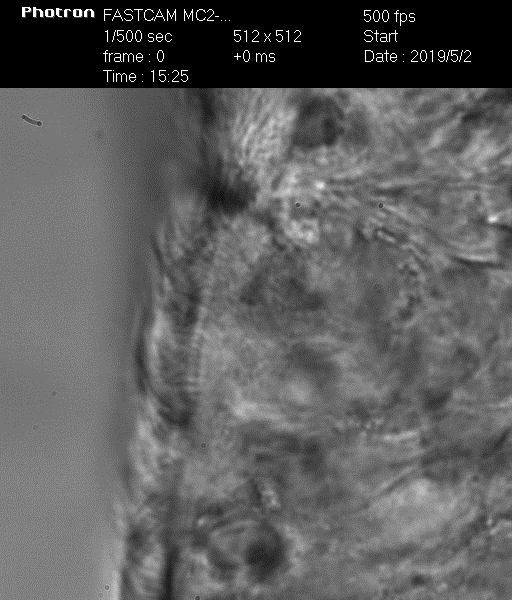

Биение ресничек у здорового – видео 1

Биение ресничек у больного ПЦД – видео 2